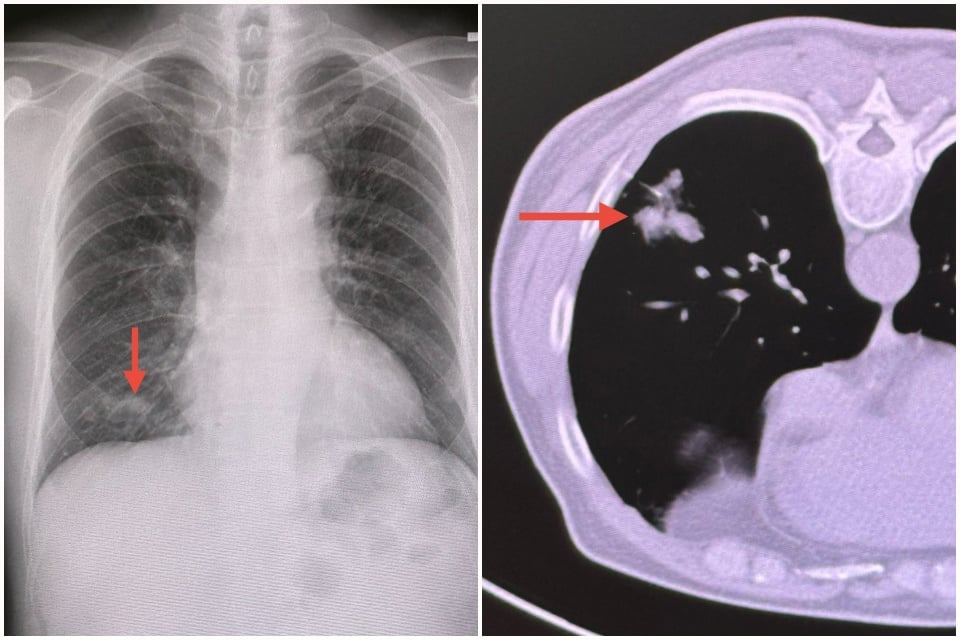

ตรวจร่างกาย ไม่มีไข้ ฟังปอดปกติ เอกซเรย์ปอดมีฝ้าขาวเล็กน้อยที่ปอดข้างขวาด้านล่าง (ดูรูป) ทำคอมพิวเตอร์ปอดเห็นฝ้าขาวที่ปอดข้างขวาด้านล่าง ส่องกล้องเข้าไปในดูในหลอดลม ไม่พบอะไรผิดปกติ ส่งน้ำล้างหลอดลมเพาะเชื้อ พบเชื้อราคริปโตค็อกคัส ใช้เข็มเจาะปอดบริเวณที่เป็นฝ้าขาว (ดูรูป) ส่งชิ้นเนื้อตรวจพยาธิวิทยา พบเชื้อราคริปโตค็อกคัส ตรวจเลือด คริปโตค็อกคัสแอนติเจน และ anti-HIV ให้ผลลบ

วินิจฉัย: ปอดอักเสบจากติดเชื้อราคริปโตค็อกคัส

ให้การรักษาด้วยยาต้านเชื้อรา fluconazole กิน 6 เดือน ติดตามเอกซเรย์ปอด ฝ้าในปอดข้างขวาด้านล่างหายเป็นปกติ